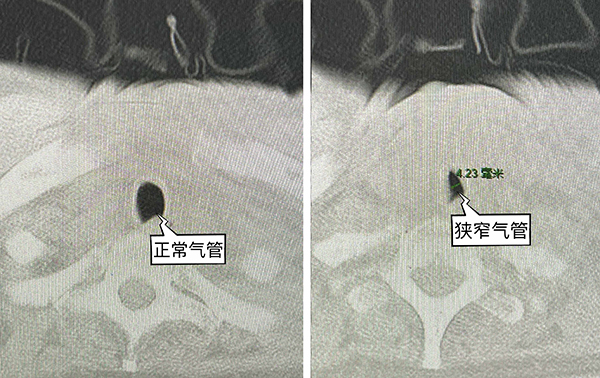

對(duì)于身經(jīng)百戰(zhàn)的手術(shù)醫(yī)生及麻醉醫(yī)生來(lái)說(shuō),這本身是一臺(tái)常規(guī)的手術(shù)。然而火眼金睛的麻醉醫(yī)生在術(shù)前的例行訪視時(shí)發(fā)現(xiàn)了一個(gè)問(wèn)題:患者肺部CT顯示有一段氣管明顯狹窄,內(nèi)徑僅4mm左右,小于適合成人的各型號(hào)氣管導(dǎo)管內(nèi)徑,存在明顯的氣管插管困難。這就給麻醉帶來(lái)了不小的挑戰(zhàn),如果麻醉誘導(dǎo)后插管失敗,患者的處境將會(huì)十分危險(xiǎn)。